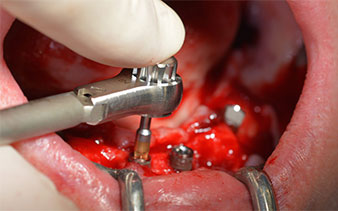

The next programmed setting is already for placement of the implants. In our practice we usually employ a torque of 32 Ncm to place the implants (Fig. 12 and 13).

High primary stability is an absolute requirement for an immediate restoration. In order to achieve this, the hole was not tapped in this case. The W&H Implantmed drill unit used here is equipped with a suitable special mode for this, which can also be directly selected and is indispensable for many indications. The final revolutions when placing the implants exceeded the value of 32 Ncm and were performed by hand. In such cases, we recommend utilizing the implants’ self-tapping function and twisting the implants backwards and forwards several times. This allows the implant to approach the final position gradually without exerting excessive pressure on the bone (Fig. 14).